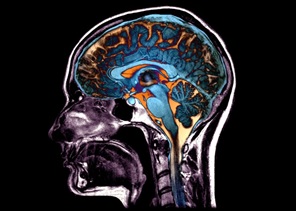

Một số phần của não bộ có xu hướng teo lại và biến dạng (ảnh: Zephyr/SPL).

Theo TS Christos Davatzikos, chuyên gia hình ảnh y sinh tại Đại học Pennsylvania (Hoa Kỳ), lão hóa không chỉ gây ra tóc bạc mà còn dẫn đến những thay đổi trong cấu trúc não bộ có thể nhìn thấy qua các hình ảnh chụp cộng hưởng từ (MRI). Nhưng những biến đổi này là rất nhỏ, vì vậy mắt người không thể nhận ra các mô hình thay đổi trong não có liên quan đến sự suy giảm này.